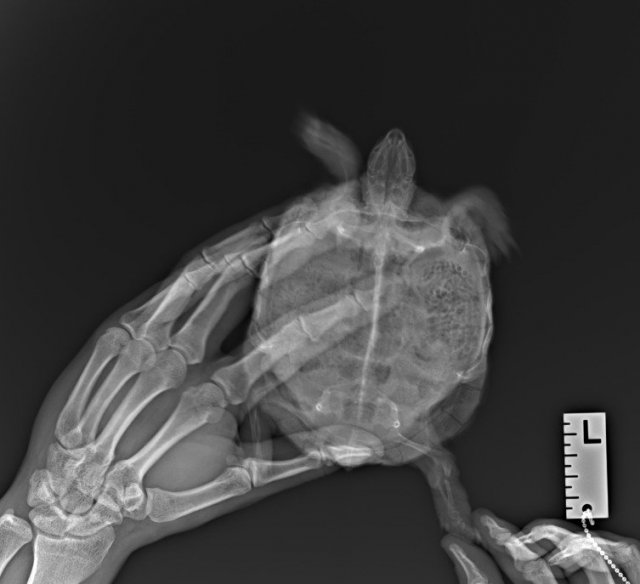

Решили таки сделать остеосинтез,ибо перелом застарелый и с простой фиксацией шансов ещё меньше.Тоже конечно хорошего мало.Лапа зафиксирована,но зафиксирована "внутрь"(фотку приложил).Вся процедура вместе с наркозом длилась пять часов,сейчас бедная лежит,отходит от наркоза.

Шансы на спасение ноги 50/50,а учитывая пожизненное "везение" Дуси - чаша клонится в печальную сторону.Но надежды не теряем,будем биться до конца.

Дуся остеосинтез    27.04.2024.jpg

20240627_195654.jpg